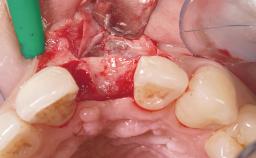

Bone Augmentation Horizontal|Simultaneous

Augmentation Materials Autogenous chips|Membrane

Placement Protocol Immediate implant placement

Socket Integrity Sufficient, with intact bone walls

Bone Volume Sufficient, with intact walls